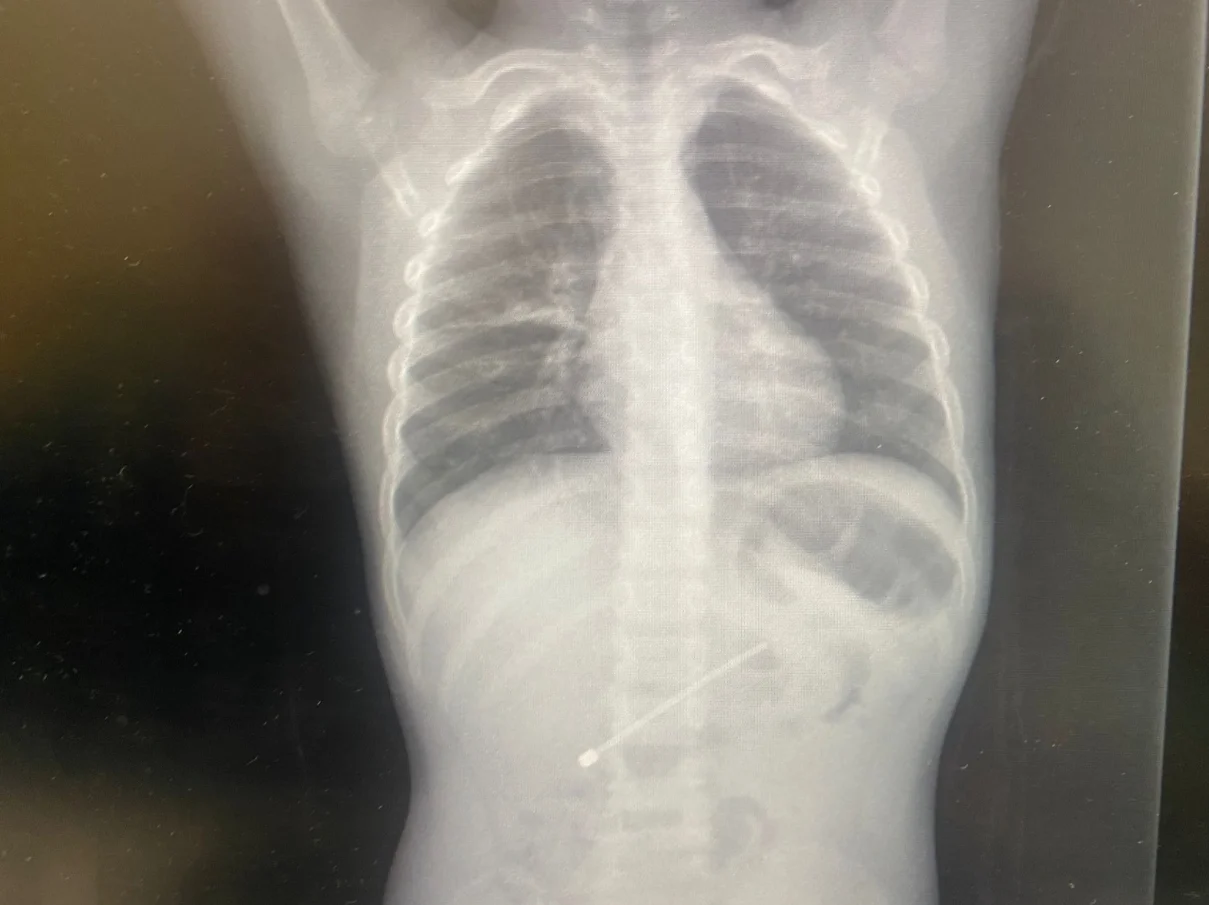

המקרה האחרון אירע היום (חמישי), כאשר אנטנה של מכשיר אלקטרוני, באורך 7.5 ס"מ, נשלפה מגופו של ילד כבן חמש. הילד טופל על ידי צוות המכון לגסטרואנטרולוגיה ותזונה לילדים ברמב"ם, שהוציא את הגוף הזר מגופו באמצעות טשטוש.

במכון אמרו כי "עצם שבנוי באופן הזה ונבלע, לא יכול היה לצאת מגוף הילד באופן טבעי מבלי לגרום לו לנזק מסכן חיים בדרך". לדבריהם, "הליך פולשני לשליפת העצם באופן מבוקר, היה הכרחי".